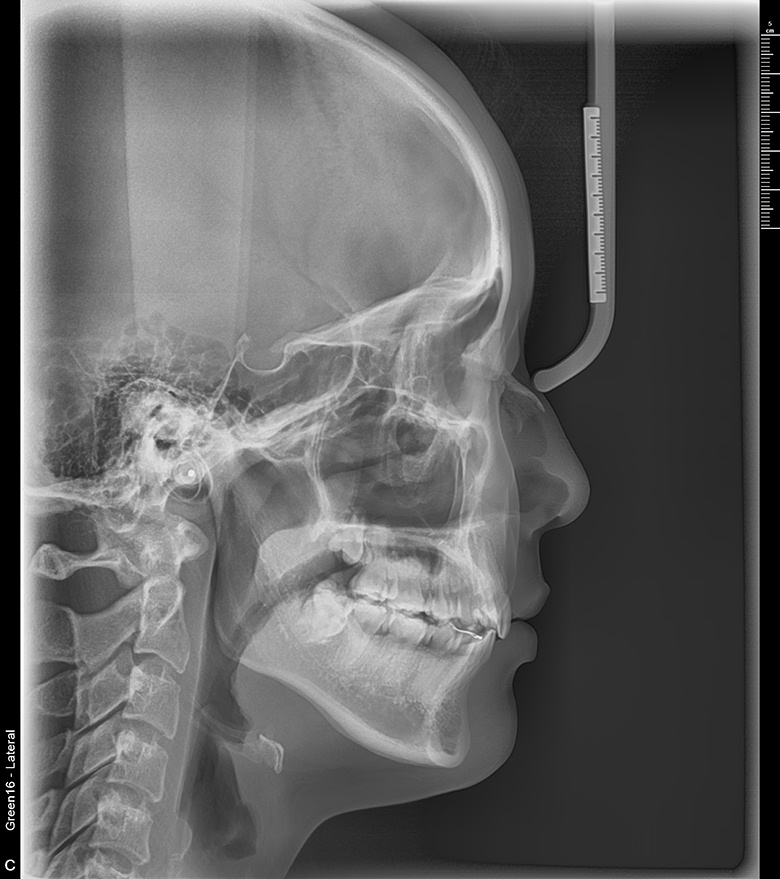

치료 후 사진입니다.